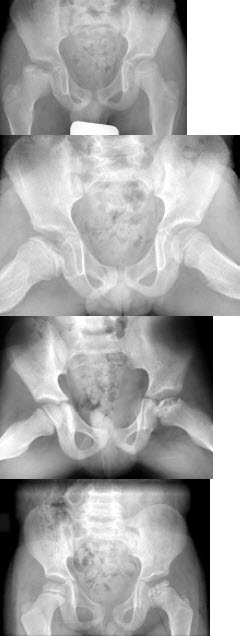

男,32岁,因车祸致右髋关节肿痛,活动受限摄片如图示,最可能的诊断是()

A.骨盆Ⅰ型骨折

B.骨盆Ⅱ型骨折

C.骨盆Ⅲ型骨折

D.骨盆Ⅳ型骨折

E.以上均不是

男,60岁,因双髋关节反复疼痛2年余,无明显外伤史,X线摄片如图,最可能的诊断是()

A.双髋关节退行性骨关节病

B.双髋关节创伤性关节炎

C.双髋关节特发性骨关节病

D.双髋关节结核

E.神经性关节炎